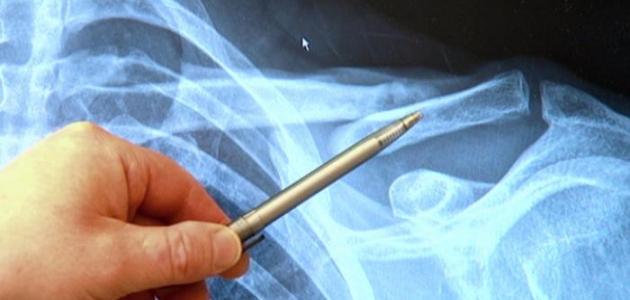

عمون - عظمة الترقوة هي العظمة التي تربط لوح الكتف بعظمة القص في الصدر، وتعتبر من أكثر المفاصل حركة في جسم الإنسان، وبالتالي فهي عرضة للإصابة والألم. قد تحدث الألم في عظمة الترقوة نتيجة عدة أسباب، بما في ذلك:

لتشخيص ألم وكسور عظمة الترقوة، يقوم الطبيب بتقييم التاريخ الطبي للمريض وإجراء الفحص السريري. قد يتطلب التصوير بالأشعة السينية أو التصوير بالرنين المغناطيسي لتأكيد التشخيص.